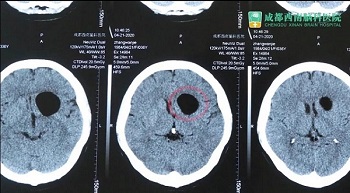

张女士 36岁 左前颅底肿瘤

患者辗转多院后来到我院,经门诊医生进行流行病史调查无新型冠状病毒肺炎地区旅游集居住史,无新型冠状病毒肺炎密切接触史,无发热、乏力、咳嗽及腹泻症状,门诊血常规、CRP、 胸部cT检查,排除新冠状病毒肺炎,门诊以“左侧前颅底肿瘤”收入我科。之后在我院进行了肿瘤切除手术。

患者1月前于贵黔国际总医院,行头颅MRI示:鞍上占位,脑电图:异常脑电图(左侧颞中央区局灶性改变) 。医院建议手术治疗,遂就诊于贵州医科大学附属医院,行头颅CT:鞍上池区域占位,考虑畸胎瘤可能,建议转院手术治疗。